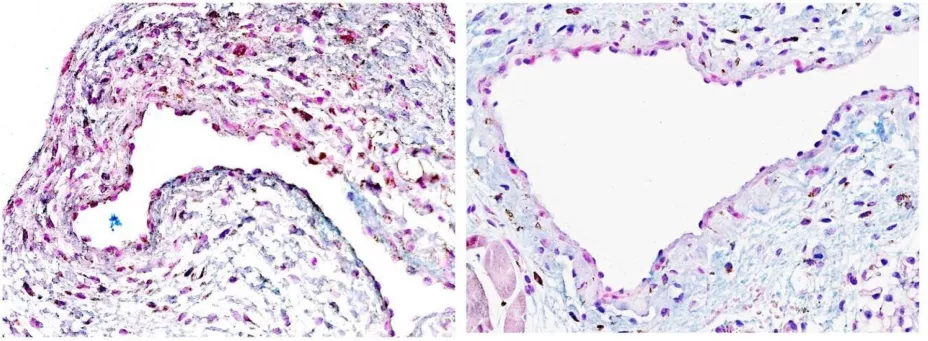

Investigadores de Mayo Clinic han descubierto que el trasplante de células madre derivadas de las propias células de grasa del paciente a la vena ayudó con frecuencia a prevenir la inflamación y el estrechamiento venoso. Esto puede ayudar a millones de personas con enfermedad renal terminal a tolerar la diálisis por más tiempo, posponiendo la necesidad de un trasplante de riñón.

Esto se debe a que estas células madre adultas, llamadas células madre mesenquimales, secretan factores de crecimiento reparadores que parecen ser eficaces en determinados pacientes con FAV, según explica el Dr. Sanjay Misra, radiólogo intervencionista en Mayo Clinic y autor principal del estudio publicado en Science Translational Medicine.

En este estudio, 21 participantes recibieron fístulas arteriovenosas (FAVs) como parte de un ensayo clínico de fase 1. Once participantes recibieron inyecciones de células madre mesenquimales obtenidas de sus propias células grasas antes de la cirugía de FAV; 10 formaron parte del grupo de control. Las FAVs cicatrizaron más rápido y fueron más duraderas en la mayoría de quienes recibieron las células madre. Sin embargo, no todos respondieron al tratamiento.

Los investigadores identificaron factores genéticos específicos con acción antiinflamatoria en aquellos que respondieron bien a las células madre. Afirman que estos biomarcadores genéticos pueden ayudar a predecir qué pacientes tienen más probabilidades de beneficiarse de esta aplicación de células madre, así como ayudar a seleccionar opciones de tratamiento personalizadas. Los investigadores esperan obtener más información a través de ensayos clínicos a gran escala.